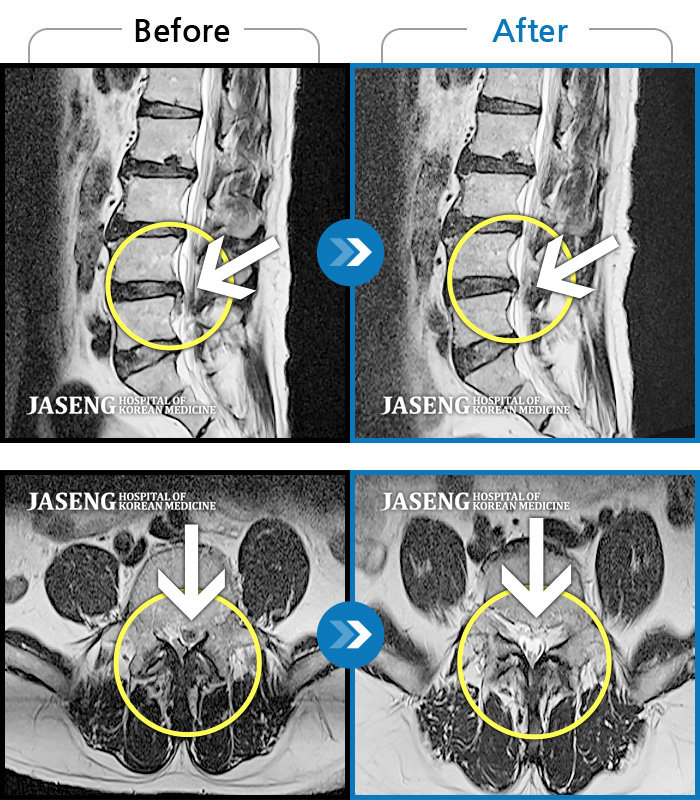

MRI 치료사례

앉아있다가 일어서면 왼쪽 다리와 발목이 당긴다.